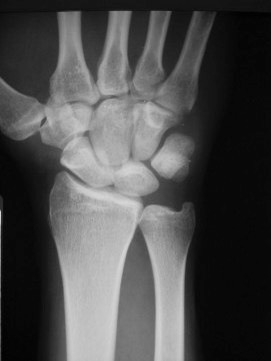

This X-ray shows the normal orientation of the bones in the wrist.